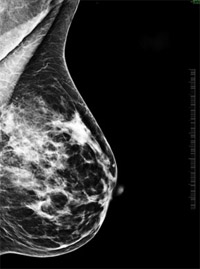

Mammográfia

A mammográfia a mell radiológiai vizsgálata: ez egy speciális röntgenvizsgálat, amelynek segítségével időben felfedezhetők a mell rosszindulatú daganatos elváltozásai. A mammográfia során alkalmazott röntgensugárzás a hagyományos röntgensugárnál jóval energiaszegényebb (lágysugár) - ez teszi lehetővé a puha mellszövet képi megjelenítését. Az emlőkről két irányból két-két röntgenfelvétel készül: egyszer felülről lefelé és egyszer ferdén. Az expozíciós idő a mellszövet esetében másodpercnyi nagyságrendű, ezért a páciensnek mozdulatlannak kell maradnia a felvételek készítése közben, különben életlen képet kapunk. A mozdulatlanságot biztosítandó, és azért, hogy a sűrű emlőszövet a sugarak számára átjárhatóbb legyen, a kúp alakú mellet két plexilemez közé helyezzük, így kisebb sugármennyiség is elegendő a vizsgálathoz.